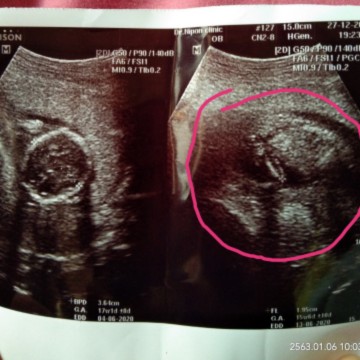

น้องเป็นชายรึหญิงค่ะ แม่ๆ

น้องเป็นชายรึหญิงค่ะ แม่ๆช่วยดูหน่อยค่ะ